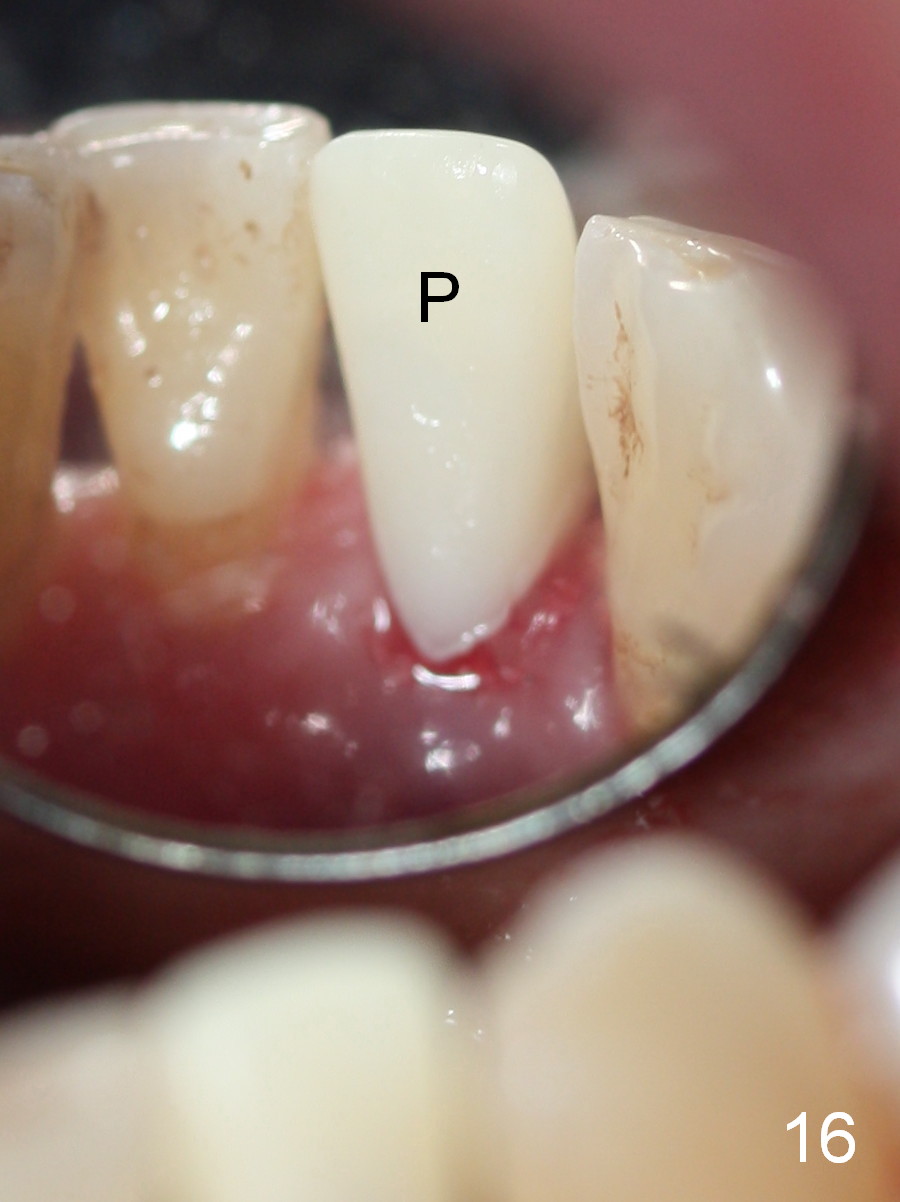

A 74-year-old man has several missing teeth (Fig.1).  His 1st goal is to replace the lower left lateral incisor (Fig.2).  The residual root has an apical lesion (Fig.3 *).  To describe intraop findings, a CT image of a different patient is used (Fig.4 coronal section; B: buccal; L: lingual).  After extraction, the buccal plate is found to be thin and low (Fig.5 arrowheads).  A 1.5 mm pilot drill (Fig.6 red line) is used to initiate osteotomy in the lingual plate of the socket.  Once the drill penetrates the lingual plate, the trajectory changes and the depth is 17 mm from the gingival margin (Fig.7).  A PA is taken (Fig.8); it appears that the osteotomy can be extended more apically.  When the pilot drill extends to 20 mm, there is sudden empty feeling.  The lingual plate has perforated (Fig.9).  A new osteotomy is established buccally (Fig.10 pink).  To avoid buccal plate perforation, especially in the buccal undercut area (>), the coronal end of the drill has to be tilted buccally (<--).  An angled abutment (3x20 mm, 15°) is placed (Fig.11,12).  The abutment is modified (Fig.13,14) to accommodate an immediate provisional (Fig.15,16 P).  Perio dressing is to be applied to prevent the bone graft from getting dislodged buccally (Fig.15).  The dressing is in place 7 days postop (Fig.17).